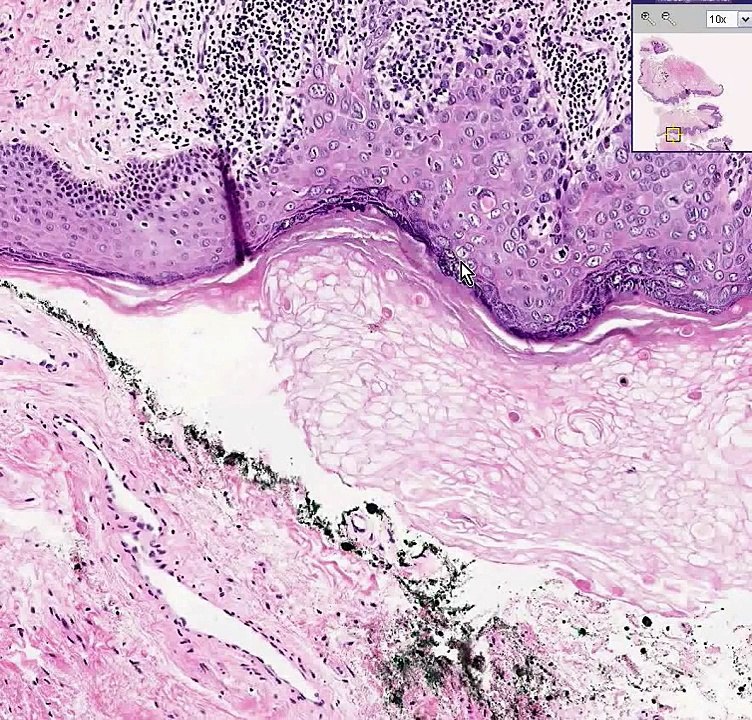

http://www.oginski-law.com Ductal carcinoma in situ is considered to be Stage 0 breast cancer. It's also known as DCIS. What is that? It's a localized breast cancer that has not yet invaded the tissues surrounding the localized lesion. Some medical experts believe this cancer does not need treatment. Others disagree. You might ask yourself, "How can anyone suggest I not get treatment for a confirmed diagnosis of breast cancer?" Watch the video to learn more. To learn more about how medical malpractice cases work in New York, I encourage you to explore my educational website, http://www.oginski-law.com. If you have legal questions, I urge you to pick up the phone and call me since I can answer your legal questions at 516-487-8207 or by e-mail at [email protected]. I welcome your call. The Law Office of Gerald Oginski, LLC 25 Great Neck Rd., Suite 4 Great Neck, NY 1021 516-487-8207 [email protected].